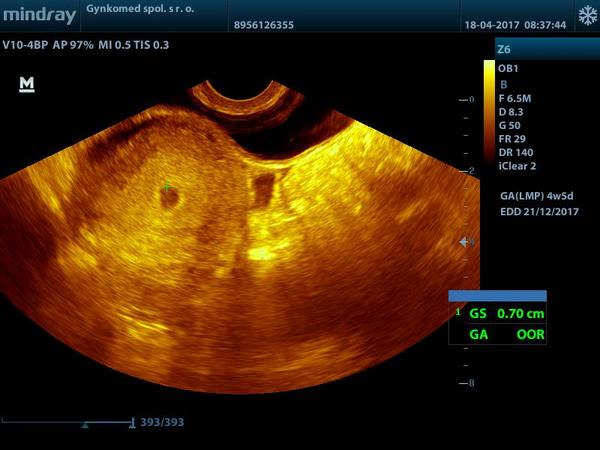

A inak som teraz pozerala papiere na tu hematologiu A tam mam písané že som V 5 tt. 🙂 takže mi to sedí zatiaľ.